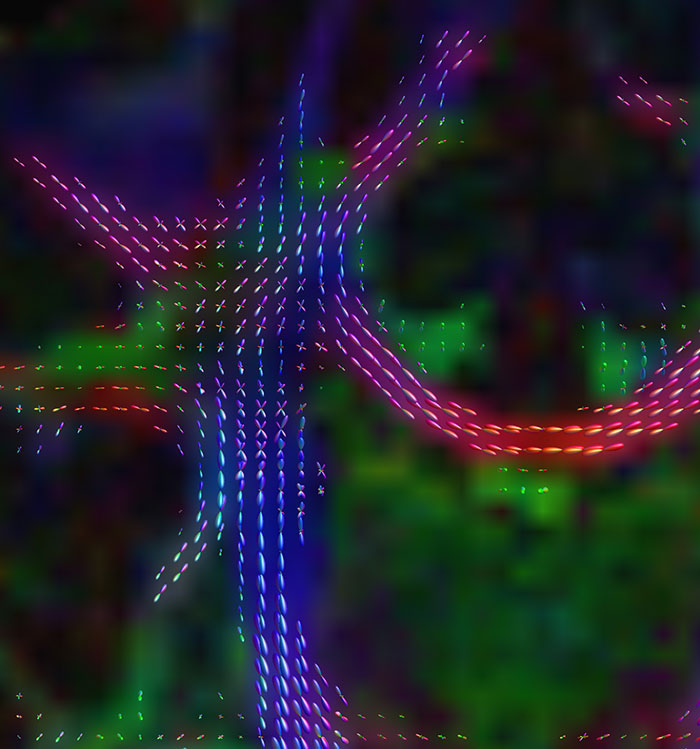

Advancing diffusion MRI

These images are produced using the ABCD protocol and illustrate the use of more sophisticated and accurate models of diffusion. The color FA maps are shown for reference. The diffusion tensor model represents the diffusion within each voxel as an ellipsoid.

Alternative models, such as constrained spherical deconvolution, better capture the rich information available with the use of high b-value dMRI and many sampling directions. In much of the brain, voxels contain multiple white matter tracts, and it is essential to capture this information to be able to perform accurate tractography and generate diffusion connectomes.

Diffusion acquisition on Achieva 3.0T dStream with matrix 140x141, 81 slices, FOV 240x240 mm, voxels 1.7x1.7x1.7 mm, TR 5300 ms, TE 89 ms, flip angle 78, MultiBand SENSE factor 3, partial Fourier 0.645, 102 diffusion directions, b-values 0 (6), 500 (6), 1000 (15), 2000 (15), 3000 (60) , scan time 2x 4:37 min. Images provided by Dr. Watts.